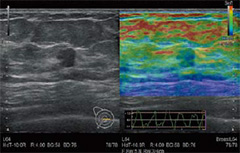

Elastography

・Real-time Tissue Elastography(RTE)

組織のひずみをリアルタイムに算出することで,硬さの違いを色付け表示します。乳腺領域をはじめ,甲状腺,泌尿器など,幅広い臨床分野での応用が可能です。

さらに,コンベックスプローブを用いてC型肝炎における肝炎Stagingの推定値(LF INDEX)を算出することも可能です。

・Shear Wave Measurement(SWM)

プッシュパルスで生体組織を振動させることによって,せん断弾性波(shear wave)が発生します。このせん断弾性波の伝搬速度(Vs)を計測することで,組織の硬さを定量的に評価できます。

・Combi-Elasto

非侵襲的に肝組織の硬さを評価するRTEとSWMが融合。肝線維化および炎症を経時的により精度高く評価できます。さらに肝脂肪化の程度を推定する指標(ATT)も同時に測定でき,肝疾患の総合的な鑑別をサポートします。